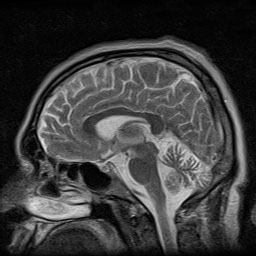

Novel missense variant in SPTBN2 possibly associated with spinocerebellar ataxia type 5 presenting as Parkinson´s disease

Spinocerebellar ataxias are a heterogeneous group of neurodegenerative diseases. There are more than 40 subtypes described so far, being spinocerebellar ataxia type 5 (SCA5) a rare autosomal-dominant ataxia with pure cerebellum involvement.  The gene responsible is the non-erythrocyte beta 2 spectrin gene (SPTBN2), encoding β-III spectrin, highly expressed in Purkinje cells. Onset is usually before 30 years, although it ranges from infancy to 70 years. The main clinical manifestations are limb and gait ataxia (> 90%); however, some patients also show trunk ataxia, sensory deficits, abnormal eye movements, dysarthria, and hyperactive deep tendon reflexes (25–90%).